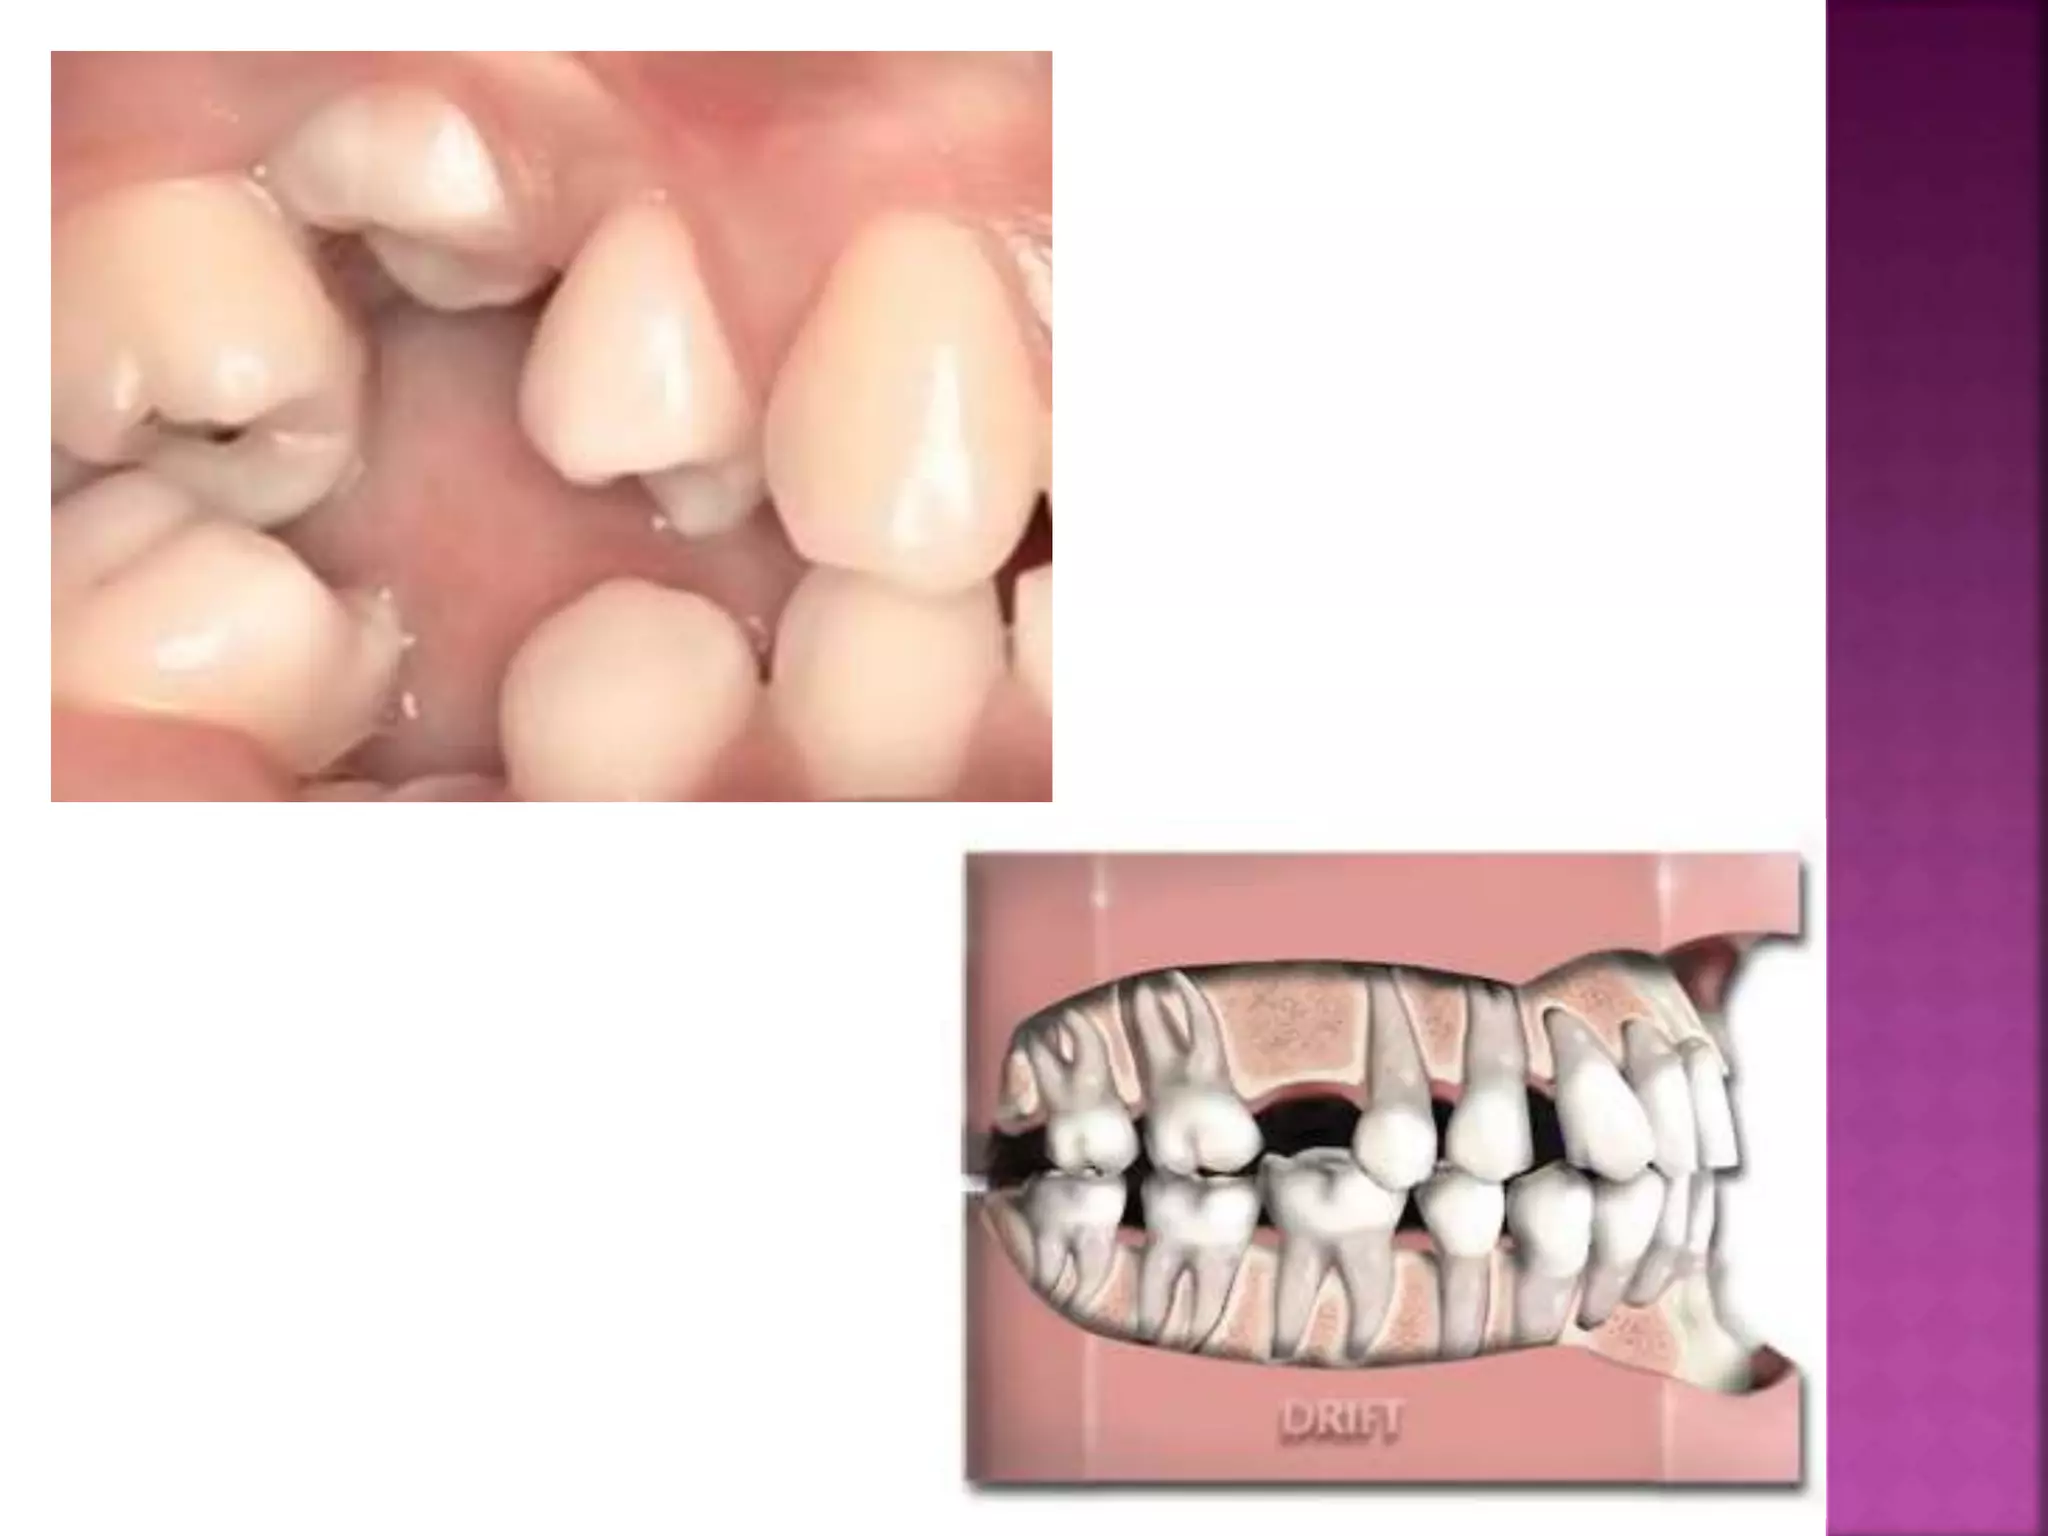

The changes onthe mesial and distal alveolar walls are correlated to a movement of all teeth toward the midline, i.e., mesial drift .

The continued occluso-mesial movementis necessary to compensate for the loss of tooth substance at the occlusal and contact surface . it is well known clinically that the contact between neighboring teeth in a complete adult dentition is maintained by a tendency for the posterior teeth to move forward.

2 - Thekey ridge or the root of the Zygomatic process which arises on the lateral wall of the maxilla over the roots of the first permanent molars and becomes the zygomatic process . It continues upwards to approximal contact .The anterior coinpenent of force on one side of the arch cancels out that of the other side in the midline provided that there is an intact dental arch. If the interproximal contacts are destroyed by loss of teeth, those behind the gap tend to drift forward, whilst those in front will lack forward development